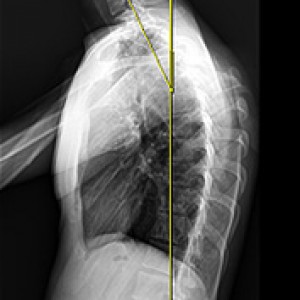

머리가 앞으로 빠질수록 목이 더 많은 하중을 견뎌야 합니다.

정상목 일자목 거북목

각도 정상 각도 15도 60도

목이 견디는 하중 5.5kg 내외 12kg 내외 28.6kg 내외

해당 사진은 수정없는 실제 치료사진입니다.

환자의 치료결과는 환자의 상태, 치료방법 등에 따라 차이가 발생할 수 있습니다.